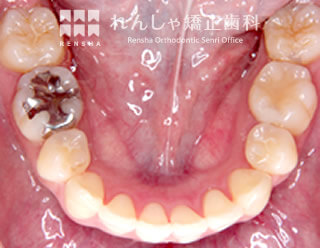

埋伏(15歳 治療期間:2年10か月)

上の犬歯が2本とも埋まったままになっていたので、スペースを確保して引っ張り出しました。

浅い位置に埋まっていたため比較的簡単に牽引することができましたが、骨の深い位置に埋まっていると治療の難易度が非常に高くなります。

| 主訴 | 上の犬歯が出てこない |

| 診断名 | Angle Class I 上顎両側犬歯の埋伏を伴う叢生 |

| 初診時年齢 | 15歳5か月 |

| 装置名 | マルチブラケット装置 |

| 抜歯非抜歯 | 非抜歯 |

| 治療期間 | 2年10か月 |

| 費用の目安 | 約89万円+消費税(検査料金、都度の処置費用等も合わせた総額) |

| リスク副作用 | 歯の移動に伴う軽微な歯根吸収、歯槽骨吸収、歯肉退縮(いずれも本症例ではほぼ無し)、矯正器具装着中のカリエスリスク増大(本症例ではカリエス発生無し) |